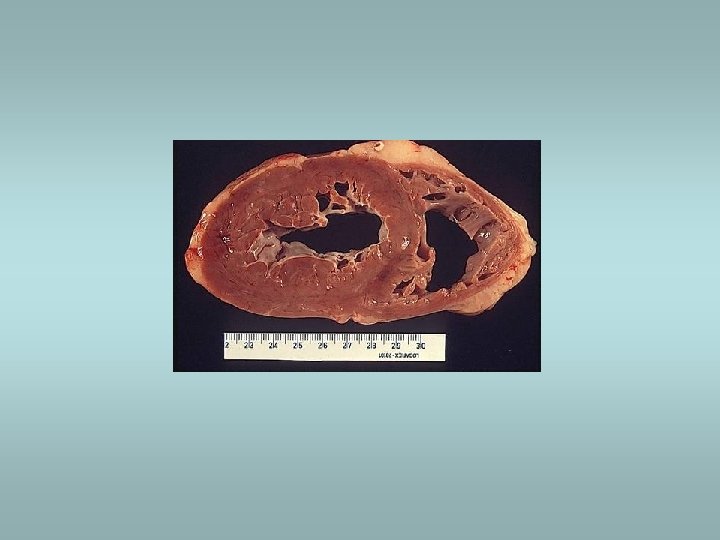

Sheehan’s syndrome ü ü ü Associated with obstetric haemorrhage or shock Caused by infarction of anterior pituitary Gonadal failure – inability to lactate ACTH, TSH deficiency Healing of necrosis – fibrous tissue